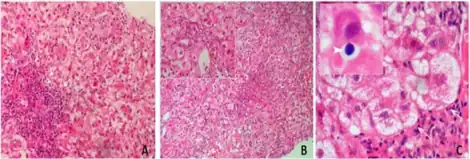

Rarely, cholestatic jaundice (also referred to as cholestatic hepatitis, a form of liver toxicity) has been associated with amoxicillin/clavulanic acid. The reaction may occur up to several weeks after treatment has stopped, and usually takes weeks to resolve. It is more frequent in men, older people, and those who have taken long courses of treatment; the estimated overall incidence is one in 100,000 exposures.[12] In the United Kingdom, co-amoxiclav carries a warning from the Committee on Safety of Medicines to this effect.[11]